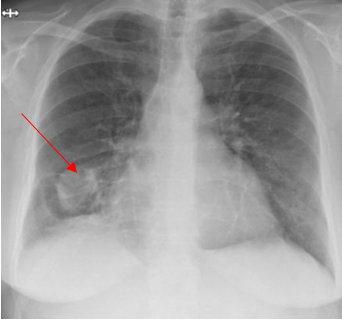

A 52-year-old Caucasian female, who is a resident of southwestern Ohio, presented to the emergency room with a chief complaint of a two-week history of right-sided chest pain, which had progressively worsened despite two courses of antibiotics and pain medications following her two recent visits to the emergency department. She also described subjective fever, shortness of breath, nonproductive cough and weight loss of 4 kg over the last two weeks. She was a smoker of ½ pack per day for 20 years and quit smoking 4 weeks ago. The patient’s past medical history includes anxiety, depression, gastroesophageal reflux disease, hypertension, mitral valve prolapse, and migraine headache. Her chest pain started in early September, and it was described as stabbing and pleuritic, which was also noted to be reproducible to palpation of the chest wall. She was seen first at the emergency department two weeks prior to the current presentation for evaluation of the right-sided chest pain. Still, at that time, there was no fever or cough, and her vitals were stable with Oxygen Saturation 94% on room air, although her laboratory testing was significant for leukocytosis with (WBC):16.6 K/UL with 68.5% neutrophils. Chest-X-ray demonstrated an infiltrate in the right lung base medially, while CT–chest angiography demonstrated no evidence of pulmonary embolism and right middle lobe consolidation consistent with pneumonia. There was no mediastinal or hilar lymphadenopathy, (Figures 1 and 2).

Figure 1. Portable Chest X-ray showing infiltrate in right lung base medially.